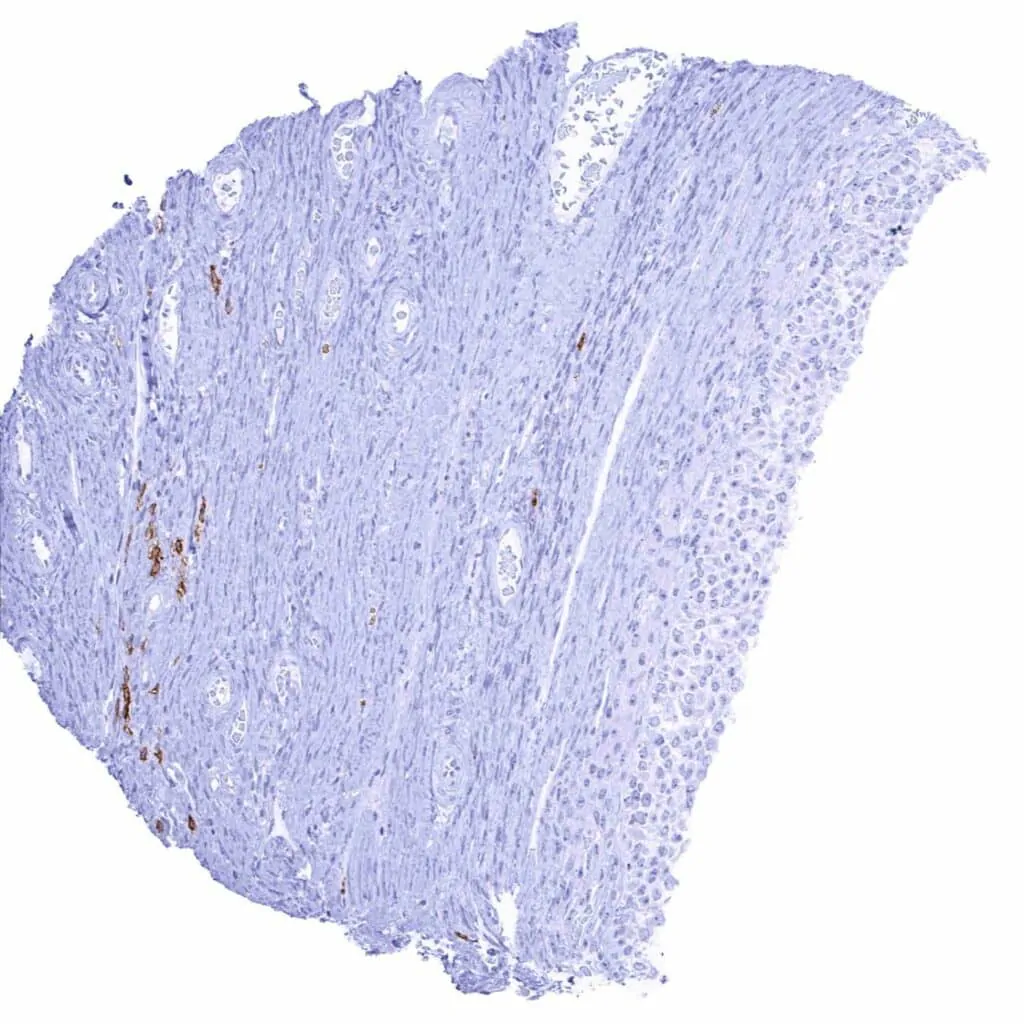

Uterus, ectocervix